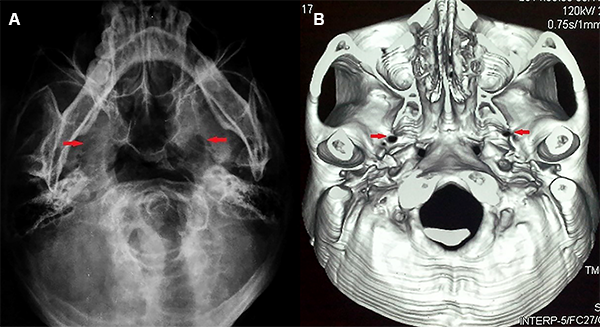

La resonancia magnética de encéfalo fue realizada con una combinación de tres secuencias de alta resolución (3D ponderada en T2, 3D TOF-MRA y 3D T1-Gad) para la detección de un posible contacto neurovascular con cortes finos en los nervios trigéminos. Los agujeros ovales fueron evaluados con radiografías o tomografía computarizada de base cráneo (Figura 2A y 2B).

Figura 2: (A) Radiografía en incidencia de submento-vértical. (B) Tomografía computarizada con reconstrucción 3D de base del cráneo. Las flechas muestran los agujeros ovales.